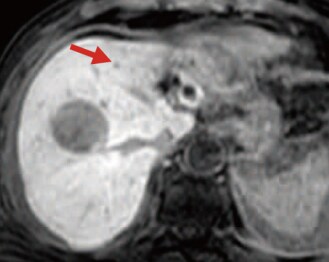

EOB-MRI findings

EOB-MRI performed after 8 days, with T1-weighting, showed, in the S8 tumor, a low signal when in phase, and a decreased signal in the right-side part of the tumor when out of phase, suggesting fat deposition. T2-weighted imaging showed a high signal (image not shown). In the arterial-dominant phase (d), the left part of the tumor showed early-stage dark staining, and in the hepatobiliary phase (e) the right-side part showed a distinct low signal, and the left part showed a slight low signal. In addition, the tumor in S4 showed a low signal in the hepatobiliary phase (f; red arrow), and intraperitoneal hemorrhage had decreased. After 18 days, cTACE was performed with the S8 and S4 tumors, using a suspension containing 8 mL of lipiodol, 30 mg of epirubicin, and 6 mg of mitomycin C, and a GS. Simple CT 1 week later (g) showed high-concentration accumulation of lipiodol in the tumor, except for the region with fat deposition.